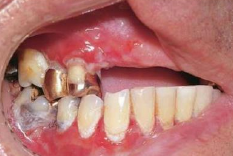

Papillon-Lefèvre Syndrome GENE: cathepsin C gene 手掌與腳底

• Cathepsin C: 溶酶體內蛋白酶

• 手掌與腳底的角質化

• 皮膚病灶的治療:維 A 酸類(systemic retinoids)

• PMN 功能不足 → 嚴重牙周病

• 快速的骨流失 → floating in air

• 瀰漫出血與增生性牙齦炎